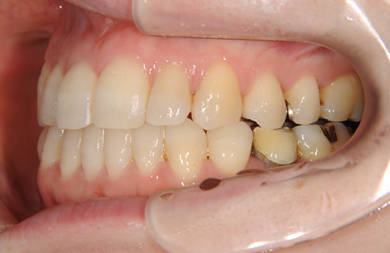

| 性別/年齢 | 女性 / 31歳 | ||||||||||||||||||||||||||||||||

| 主訴 | 歯並びを綺麗にしたい。 | ||||||||||||||||||||||||||||||||

| 治療方針 | 口元がきれいなので、なるべく横顔を変えないように歯を抜かずに治療を行う。しかし、下顎がだいぶ前に出ていて、上下の顎の前後的な位置のずれが大きいため、下顎にはインプラントアンカーを用いて、下の歯を本来の位置まで後ろに引っ張って治す。 | ||||||||||||||||||||||||||||||||

| 治療内容 | 唇側矯正(シルバー)、保定装置、矯正用スピードインプラント2本 | ||||||||||||||||||||||||||||||||

| 治療期間 | 1年5ヶ月 |